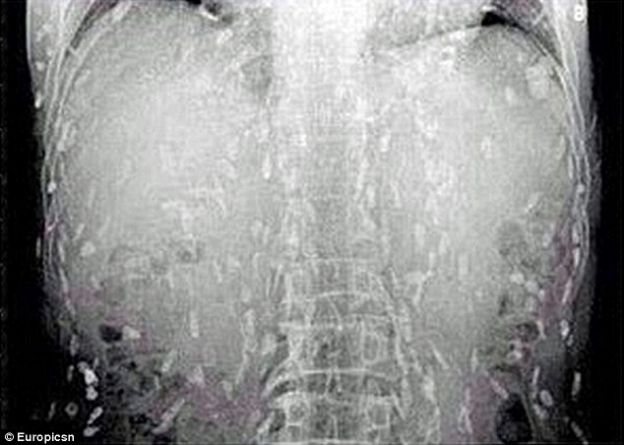

Este hombre se vio enfrentado a horribles consecuencias por comer alimentos infectados.

Después de explicar sus síntomas y para el horror de todos, los rayos X revelaron que tenía el cuerpo invadido de tenias.